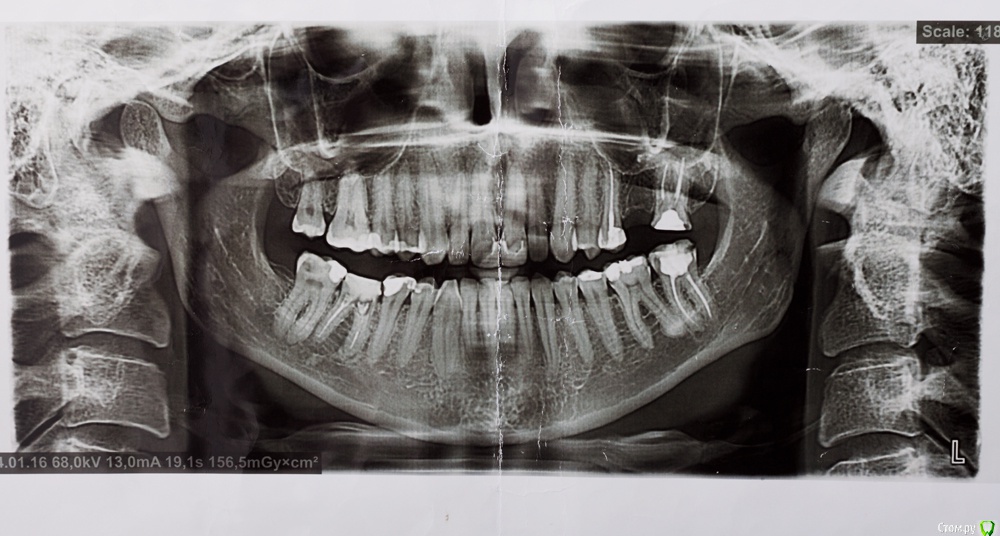

венди Опубликовано 26 января, 2017 Поделиться Опубликовано 26 января, 2017 (изменено) Добрый день! Не знаю в какой раздел будет правильно добавить, т.к. проблема смешанная. Помогите, пожалуйста! 3 месяца мучений. В прошлом году начала заниматься зубами. Был сделан панорамный снимок (прилагаю).В мае в районе отсутствующего 26 был установлен имплант с одновременным открытым синус-лифтингом. Послеоперационный период протекал более-менее нормально. Меня отпустили на пол года. И я стала заниматься остальными зубами. Лечили кариес справа, был удален 46 (резорбация мед. стенки медиального корня с перфорацией). К осени добрались до левой нижней стороны. 26.09. - был залечен кариес в 36 зубе. После этого зуб стал стрелять током при накусывании. Врач решила ещё понаблюдать.19.10. - 37 зуб с гранулемой был распломбирован, врач прошла каналы, заложила кальций. Через 6 дней ещё раз все прочистили, запломбировали каналы полностью, поставили временную пломбу и сказали, что можно протезироваться. Вроде зуб после лечения не беспокоил.01.11. - я пошла на осмотр к хирургу по поводу удаленного 46. Хирург решил раскрыть имплант, т.к. уже время подошло. Сказал всё хорошо прижилось и поставил формирователь десны. С этого дня моя жизнь разделилась на до и после.. Стала болеть вся область вокруг импланта, появилось ощущение мешающего валика под щекой, формирователь утонул в десне, отечность в этой области была. Обобщу и скажу, что после этого формирователь перекручивался еще 3 раза, внутри все промывалось, я принимала антибиотики. Острые ощущения немного ушли, но дискомфорт мешающий нормально жить оставался. По снимку - все отлично, имплант интегрирован (прилагаю). Одновременно с этими манипуляциями с имплантом 36 зуб стал не только бить током, а до него уже нельзя было дотронуться. 18.11 - вскрыли, депульпировали, заложили кальций и через неделю закрыли все постоянной пломбой (снимок прилагаю). Всё это время, впрочем как и сейчас вся левая сторона была охвачена ужасными ощущениями. Распирание, нытье, давящая боль, дискомфорт и днем и ночью. Стала плохо спать. Перед Новым Годом хирург принял решение выкрутить формирователь и посмотреть за динамикой. Мне показалось, что стало немного легче, особенно что касается ощущение валика под щекой. НО все равно с левой стороны мне что-то болит. От области импланта ли это идет или от 36-37 - я не знаю, не могу точно дифференцировать.... т.к. ковырялись везде одновременно и у меня уже все спутано... Никто не может понять, что со мной, т.к. по снимкам и 3Д все отлично. На прошлой неделе придя в очередной раз в клинику - по панорамному снимку и моим жалобам на боли поставили диагноз "дисфункция ВНЧ, артроз ВНЧС слева". При этом я спокойно открываю рот без болей, щелчков и хруста, при жевании тоже ничего не болит. Назначили физио и Аэртал - принимаю больше недели вообще все без изменений... аэртал даже не обезбаливает особо. На данный момент я ощущаю постоянный тупой ноющий тянущий дискомфорт слева. Чувство распирания. Поднимается иногда температура 37-37,1. Плохо сплю, нервничаю, т.к. очень снизилось качество жизни. Помогите, пожалуйста, разобраться. На что бить, если по снимками как бы все хорошо?! Имплант, 36, 37, сустав?? Все началось с раскрытия имланта. До этого я жила обычной жизнью. Есть 3Д декабрьские. Если кто-то захочет посмотреть я добавлю. Спасибо! Изменено 26 января, 2017 пользователем венди Ссылка на комментарий